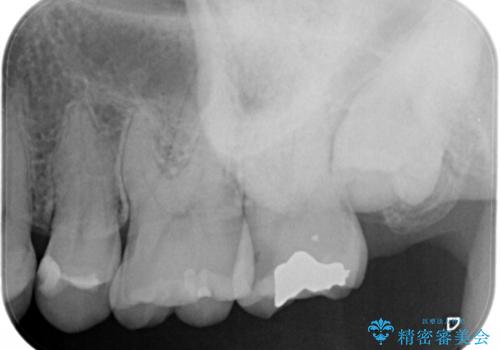

- 一番奥の歯に違和感がありご来院頂いた患者様です。

診断の結果、一番奥の歯は失活していたため精密根管治療から治療介入となりました。奥から2番目の歯にも大きな虫歯が認められたため、セラミックインレーによる補綴治療を行いました。 精密根管治療は患者様のご希望により、福本院長に行っていただきました。

根管治療をした歯は神経のある歯と比較して強度が下がり、長期的に破折のリスクが高まると言われています。破折のリスクを軽減させるため、根管治療を行った歯に対しては歯冠をすべて覆うクラウンという被せ物にて補綴処置を行います。

適合不良の補綴物は二次的な虫歯発生のリスクが高まります。